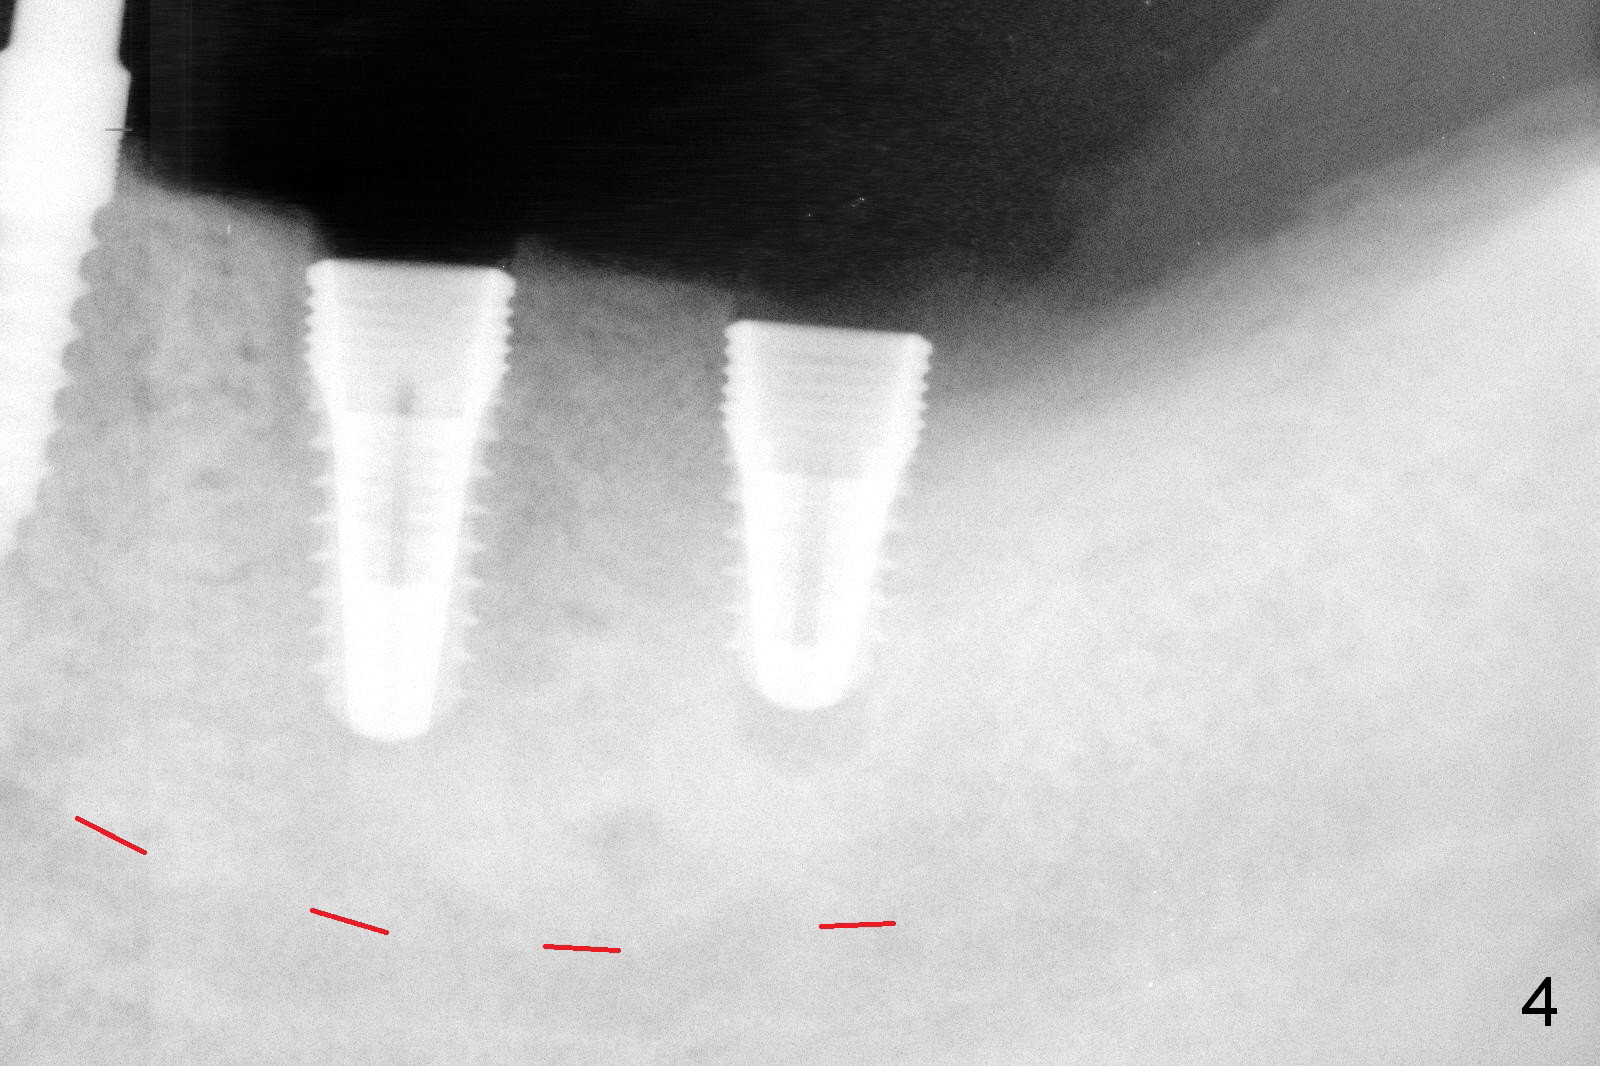

It is our instant decision to make osteotomy 2 mm deeper than the corresponding intended bone level implants so that the buccal and lingual perforation is less severe. This is the result: 4.5x8 and 4.5x10 mm implants in place (Fig.4). Later the last one is placed ~ 1 mm deeper. After placement of 6.8x4 (2) mm abutments at #18 and 19 and adjustment of abutment height, a provisional bridge is fabricated. One piece implants appear to be strong enough at sites of the lower canine and premolar. Autogenous bone harvested during osteotomy is placed around the implant at #18 and 19 where the top micro threads are exposed.